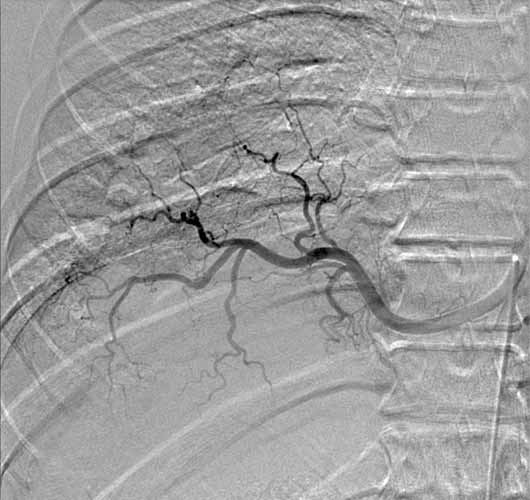

Flexible bronchoscopy revealed normal bronchial anatomy (Video 1). There was no evidence of stricture. All segmental airways were present. A right thoracotomy was performed. The sequestration appeared as a bluish mass incorporated in the substance of the right lower lobe (Figure 6). The artery supplying the sequestration was visualized coursing through the inferior pulmonary ligament and divided (Figures 7, 8; Video 2). Alternating single and double lung ventilation, the sequestration was identified along the basolateral margin of the right lung (Video 3) with a clear line of demarcation. A combination of electrocautery and 4.8mm endoscopic staplers (Video 4) was used to separate normal lung from the sequestration (Video 5). Fibrin glue was applied to all staple lines. Normal bronchial airways were not divided and the remaining lower lobe inflated normally (Video 6). The post-surgical course was uncomplicated and the patient was discharged on post-operative day four. Pathology revealed parenchymal cyst formation with chronic inflammation and organizing pneumonia.

![]() |

| Figure 6: Intraoperative image of bluish-hued sequestration | Figure 7: Feeding artery ligated and partially divided | Figure 8: Cut end of feeder artery off aorta |